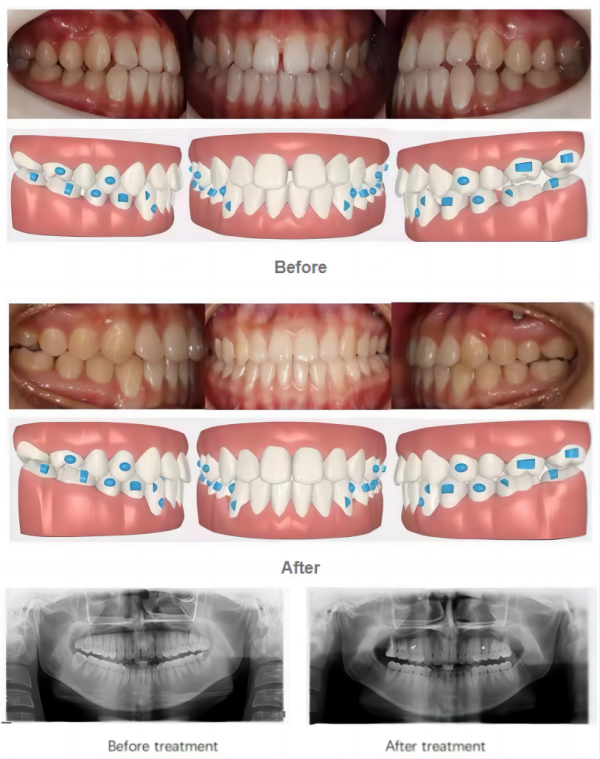

Case Study

The chief complaint of this case is crowded teeth. Our VinciSmile treatment plan designs to extract teeth 14 and 24, mesialize posterior teeth to correct it to Class II relationship, retract upper anterior teeth to correct overjet relationship and add IPR. During the process, uses vertical rectangular attachment to assist teeth retention, dental-root control and mesialization.

Through 24 months of invisible orthodontic treatment, the following results are achieved:

1. Straightened and aligned upper and lower teeth;

2. Molars have been corrected into full distoocclusion;

3. Normal overbite and overjet.